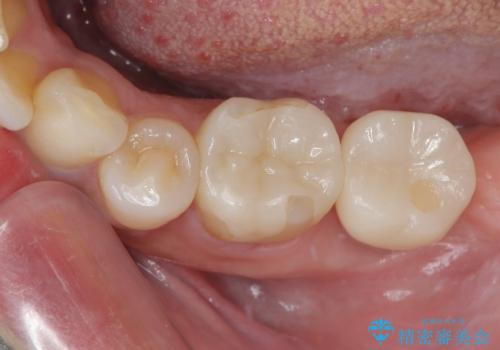

そこで今回は、抜歯即時インプラントの適応と判断しました。

抜歯と同時にインプラントを埋入し、さらにその日のうちに仮歯を装着することで、見た目と機能を即日に回復しています。